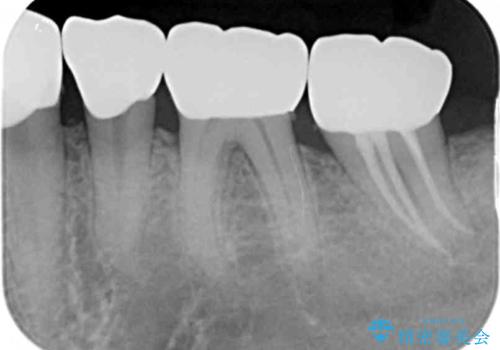

- 著しい歯ぎしりですり減ってしまった、奥歯のクラウンのやりかえを希望され来院されました。

このままの状態でクラウンのやりかえを行うと高さが低く安定の悪いクラウンとなってしまうため、事前に歯周外科手術を行い歯ぐきを下げることで安定性の高いクラウンを製作する治療計画としました。

高さの低いクラウンはセメントが漏出しやすく脱離しやすいだけでなく虫歯の再発の可能性も高まってしまいます。